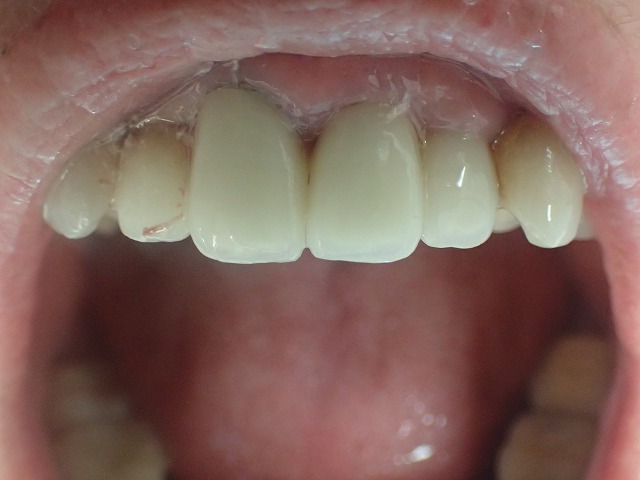

左右対称に形態修正後、磨きをかけました。

よいものは長持ちです。

20年以上前の補綴物ですが綺麗になりました。

この方の場合は歯周病処置も含めて

定期的にお手入れすることがおすすめです。